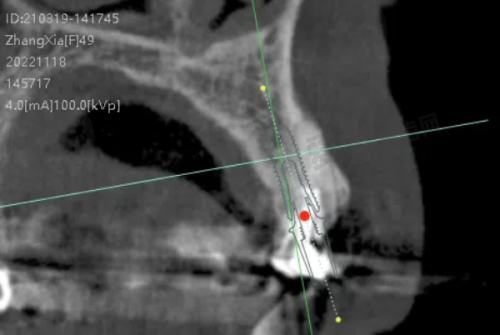

这个价格起的半口牙种植项目,包含了一系列的服务内容。首先是全方面的口腔检查。在种植手术前,贾医生会为患者进行详细的口腔检查,包括口腔X光片、CT扫描等,以正确了解患者的牙槽骨情况、牙齿缺失情况以及口腔健康状况。这一步骤非常重要,它为后续制定种植方案提供了科学依据。其次是个性化的种植方案设计。贾医生会根据检查结果,结合患者的需求和期望,设计出更适合患者的半口牙种植方案。方案中会确定种植体的品牌、型号、数量以及种植的位置等。再者就是种植手术的费用。手术过程中,贾医生会凭借不错的技术,将种植体正确地植入患者的牙槽骨内。手术采用精良的麻醉技术,确保患者在手术过程中不会感到明显的疼痛。此外,还包含术后的护理和随访服务。医院会为患者提供详细的术后护理指导,帮助患者更好地修复。同时,会定期对患者进行随访,了解种植体的愈合情况和患者的口腔健康状况。